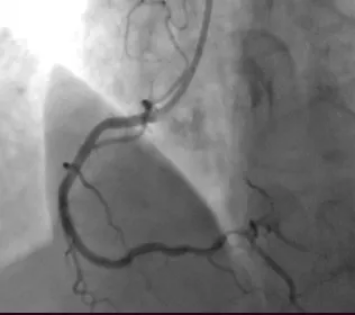

图 | 植入生物可降解支架后的右冠状动脉